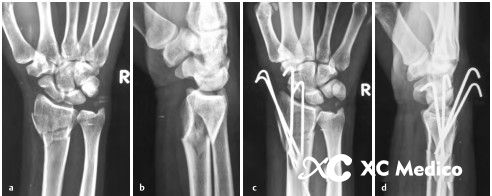

Во -первых, выполняется закрытое восстановление перелома, с медленной и непрерывной тягой, а дорсальное и радиальное смещение корректируется с помощью сгибания пальма и локтевого отклонения. После сокращения рука помещается на свернутый лист, поддерживая пальмовое сгибание и локтевое отклонение (рис. 2а, б) и фиксируется не менее трех чрескожных проводов Киршнера.

Первый K-провод вводится в бугорку Листера, наклонен при 45 ° и направлена на пальмовую кору проксимального фрагмента кости на длинной оси радиуса. Если точка вставки находится на локтевой стороне бугорки Листера, сухожилие Extensor Ollicis может быть повреждено.

Вторая K-провода вставлена 0,5 см дистальна к радиальному стилоидному процессу, K-провода находится под углом 60 ° к радиальной оси и проникает в локтевую кору, проксимальную к перелому.

Третий K-провода фиксируется к фрагменту Lunate Fossa Bone 0,5 см дистально до линии сустава запястья, расположенной между четвертым и пятым компартментами разгибателей. K-провода прикреплена к ладонильной стороне радиуса под углом 45 °, как показано на рисунках A и B ниже.

Классическая чрескожная фиксация проволоки Киршнера расстановки дистального радиуса показана на рисунках AE ниже.